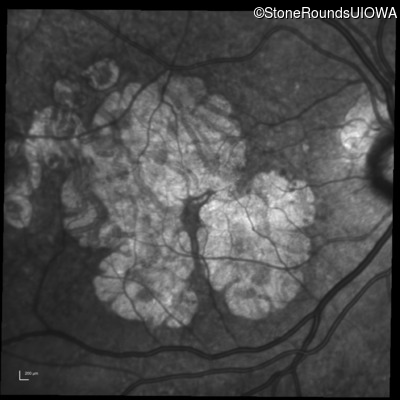

Blue Autofluorescence - Right - 20/25

Exemplar

Blue Autofluorescence - Left - 20/25 -2